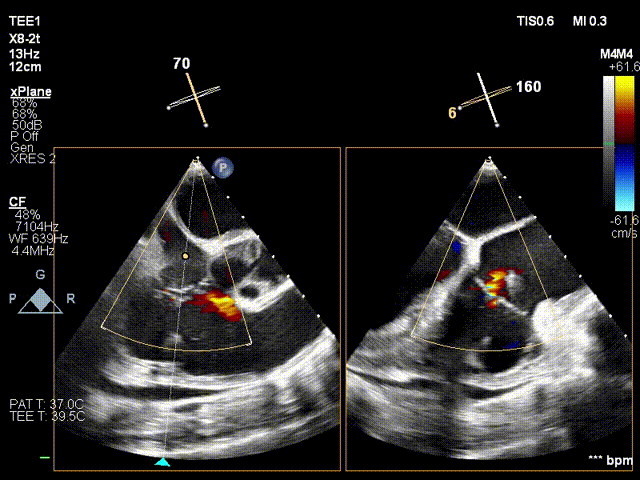

术前超声

术后超声